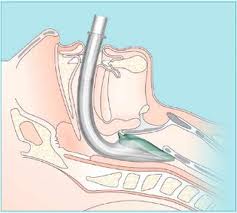

Вот так выглядит i-gel в сравнении со структурами гортаноглотки:

На рисунке:

1. Язык

2. Корень языка

3. Надгортанник

4. Черпалонадгортанные складки

5. Грушевидная ямка

6. Задняя группа хрящей гортани

7. Щитовидный хрящ

8. Перстневидный хрящ

9. Вход в пищевод.

Таким образом, при введении i-gel располагается так: